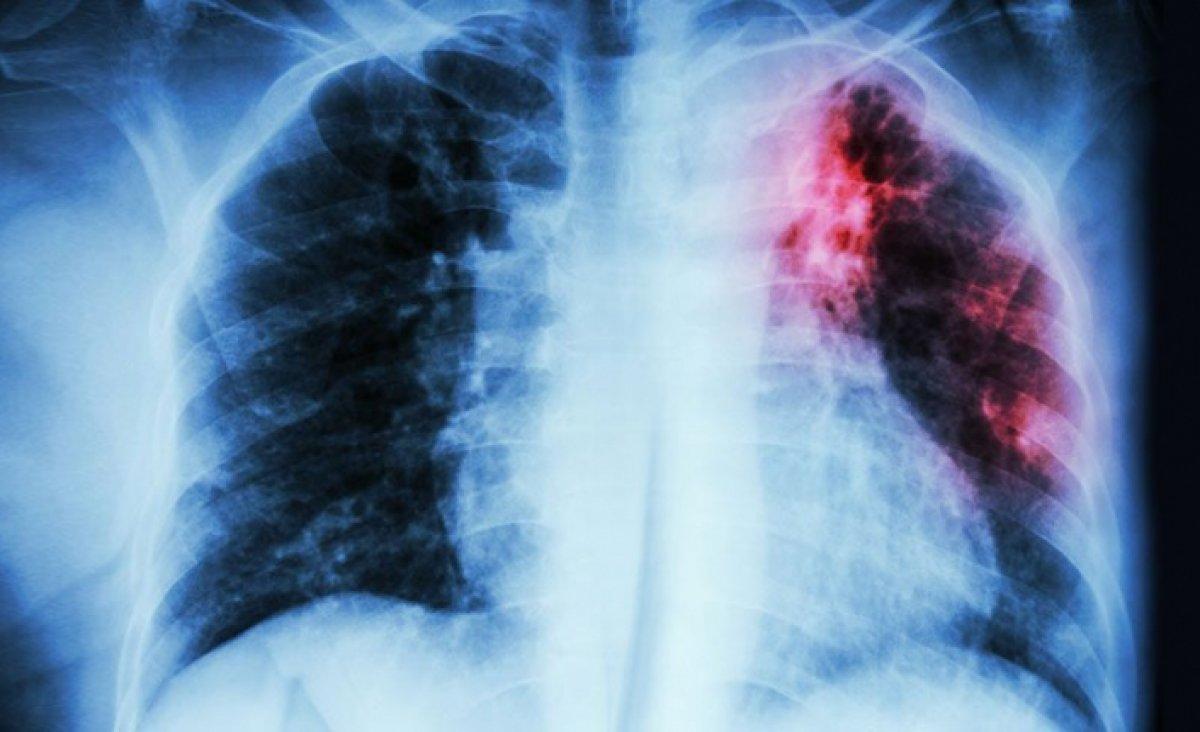

Verem hastalığı, yani tıbbi adıyla tüberküloz hava yoluyla bir bireyden diğerine yayılan, bulaşıcı bir akciğer hastalığıdır.

Verem hastalığı Mycobacterium Tuberculosis isimli bakterilerden kaynaklanır. Tedavi edilebilir ve verem aşısı ile önlenebilir bir hastalıktır.